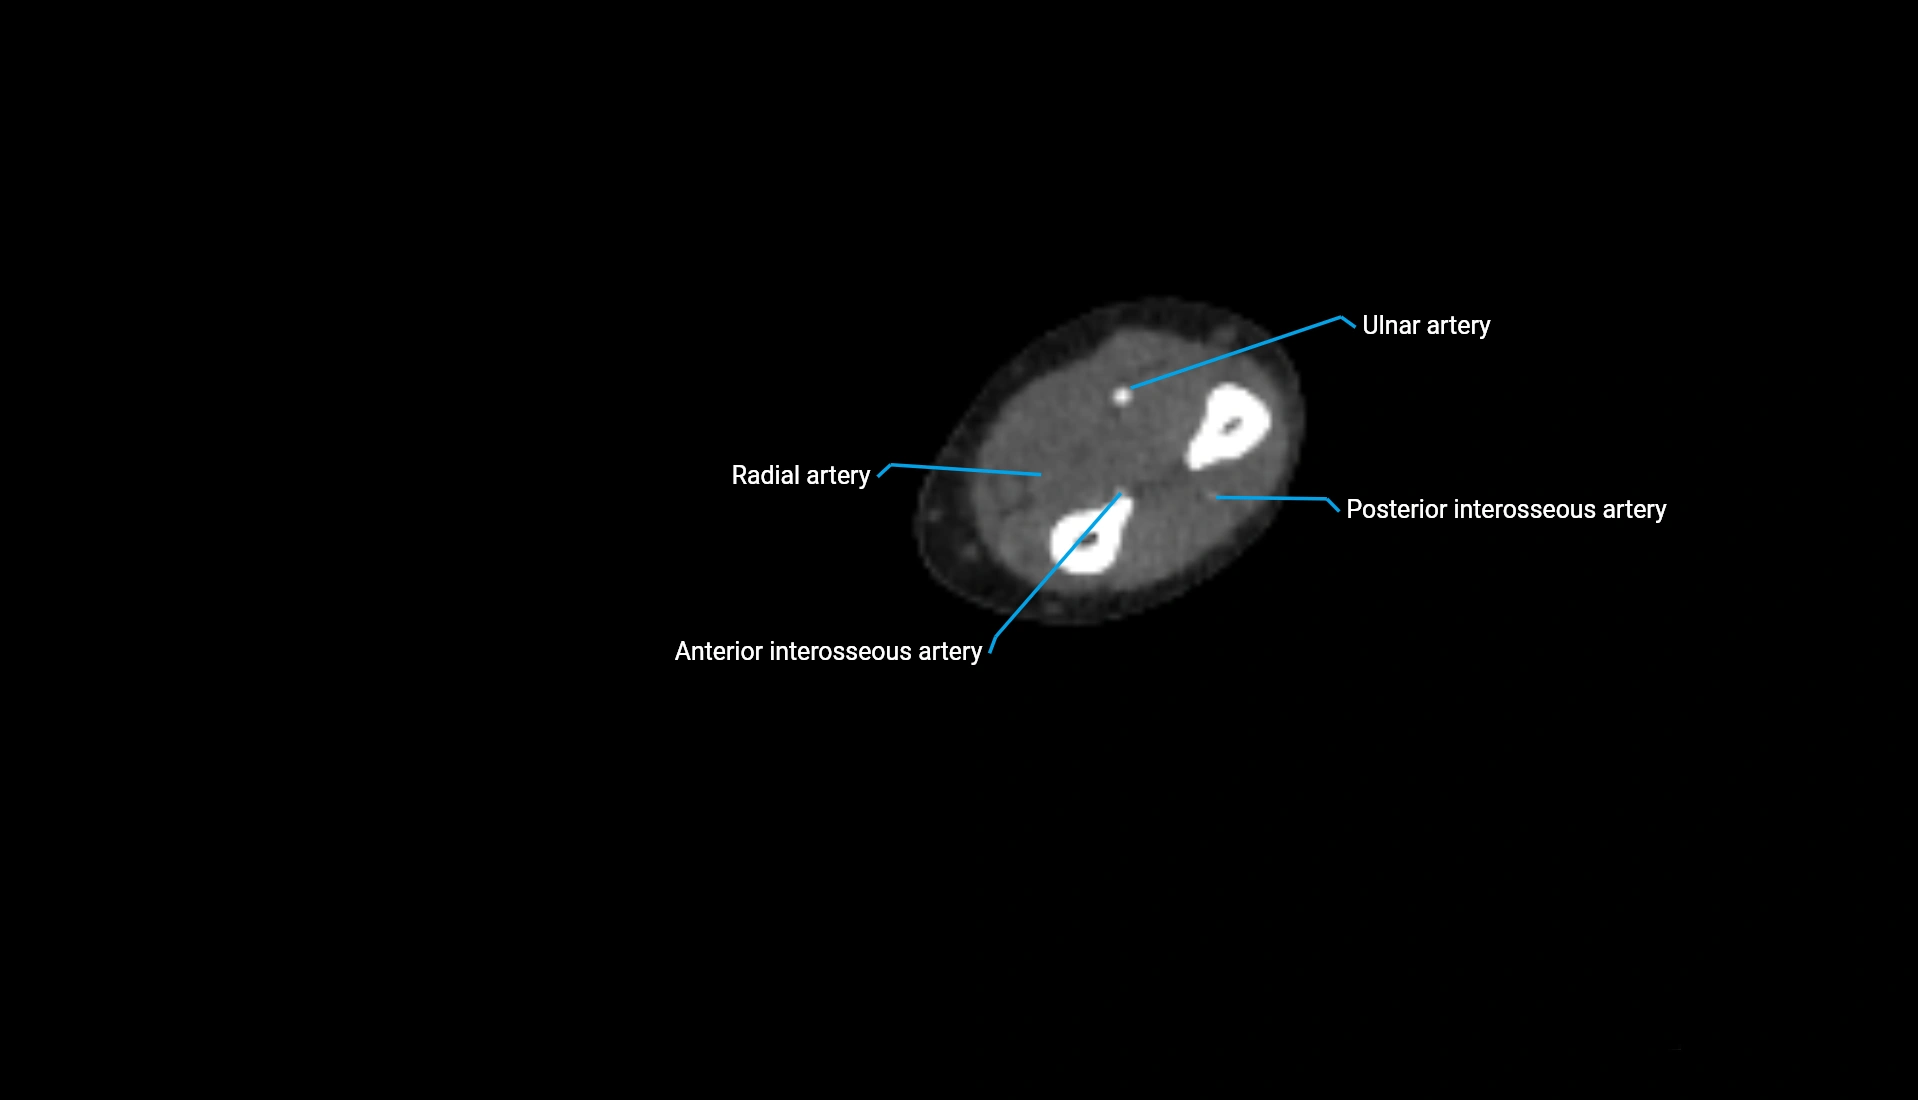

CT Appearance

Non-Contrast CT:

• Cortex: High-density, sharply defined

• Subchondral bone: Dense cancellous matrix

• Articular surface: Smooth concave contour articulating with the capitellum

• Excellent for evaluating bone integrity, alignment, and subtle fractures